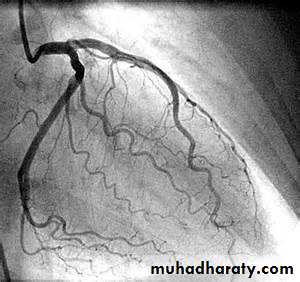

Coronary arteriography

Coronary AngiographyFor more presentations www.medicalppt.blogspot.com